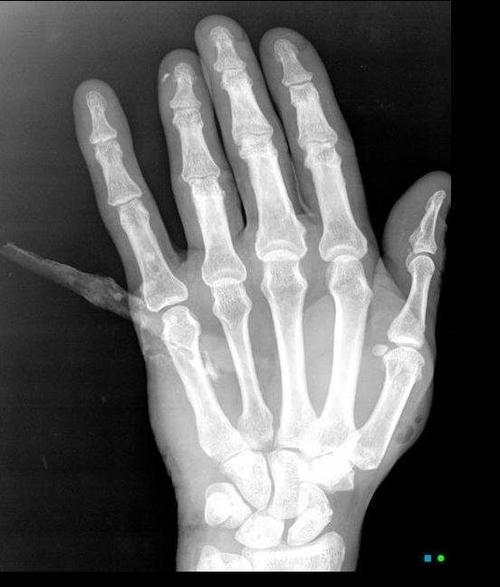

También hay varios ejemplos de heridas traumáticas, desde palos hasta balas pasando por espinas de pescado.